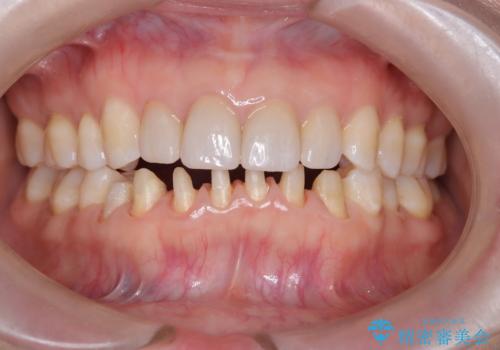

【オールセラミック】下の前歯が痛い。

- 以前に治療した前歯が痛むことを主訴に来院されました。

根っこに病気があり、根管治療から被せ物まで治療を行いました。

根管治療を行った後、3ヶ月間治癒の確認をしてからオールセラミックスペシャルで治療を行いました。